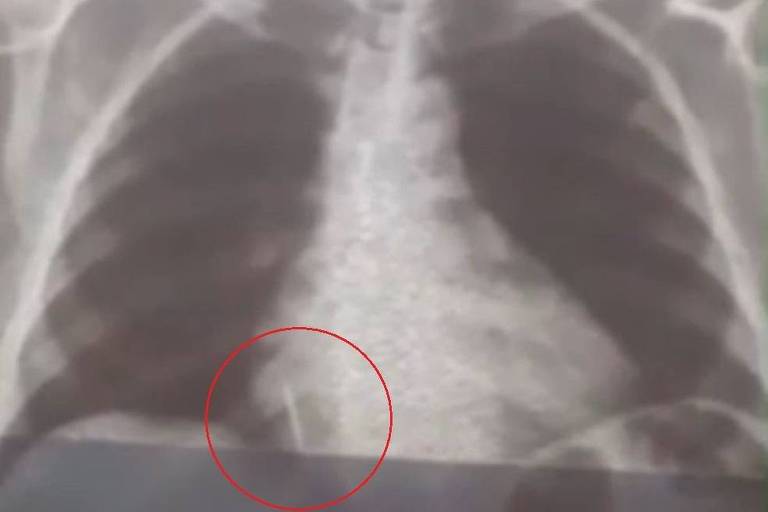

Uma mulher de 55 anos de nome Iolanda Mariano de Melo Simplício está desde o dia 26 de julho com uma broca de dentista dentro do pulmão. Após não conseguir ser operada por falta de equipamentos nos hospitais públicos da cidade, finalmente ela teve a cirurgia marcada para esta quinta-feira (26).

O caso aconteceu quando Iolanda foi extrair um dente no dentista. Em um determinado momento, a broca do aparelho utilizado pelo profissional foi aspirada e foi parar no pulmão da mulher. Esse dentista foi demitido.